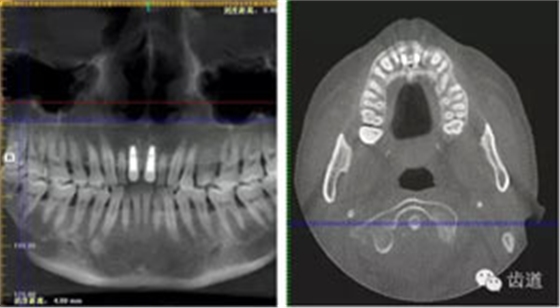

術(shù)前放射片

術(shù)后CT

戴牙后CT